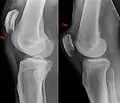

Quadriceps tendon rupture in plain X-ray: Incomplete rupture with haematoma in tendon. -

Quadriceps tendon rupture in plain X-ray -

X-ray of a tear of the patellar tendon. On the left: The kneecap is pulled up. On the right: Significant dent in the soft tissue above the kneecap. -